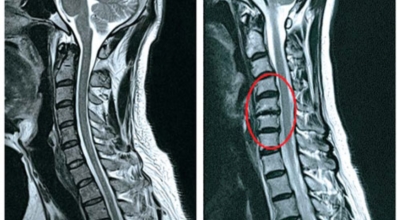

목디스크 증상이 나타날때 빨리 발견하여 비수술 치료를 받고 꾸준히 관리하는 것이 베스트이죠. 목디스크 환자 중 수술을 진행하는 환자는 2% 미만으로 현저히 적다고 해요. 수술을 진행하는 경우는 감각이 느껴지지 않는 마미증후군이나, 한쪽 다리가 눈에 띌 정도로 야윈 경우에만 진행하므로 올바른 자세 교정만으로도 충분히 호전될 수 있는 질병이죠. 목에 연관된 검사는 MRI나 CT를 이용해요. 그러나 전자의 경우 비용이 굉장히 비싸기 때문에 디스크 증세가 확실하다고 생각될 경우에만 선택적으로 하고 의무적으로 하는 건 아니니까 비용에 대해선 부담을 가지지 마시길 바래요.

목디스크 증상으로 인해 3개월 이상 약물이나 물리치료를 해도 효과가 없을 경우 수술을 고려해야 해요. 통증이 심해서 일상생활에 지장이 있거나, 신경증상이 악화되고 근력도 함께 줄어들 때와 큰 디스크가 탈출해 중추신경인 척수를 압박해 척수증이 발생하는 경우에도 수술을 고려할 수 있어요.

수술할 때는 목의 앞쪽에서 디스크를 완전히 제거한 뒤, 뼈를 이식을 하는 방법을 가장 보편적으로 사용하는 편이예요. 디스크가 세 곳 이상인 경우 목의 뒤쪽에서 수술하는 방법이 효과적이며, 수술 후에는 보통 6주에서 3개월 정도 목보조기를 착용하는 것이 좋아요.